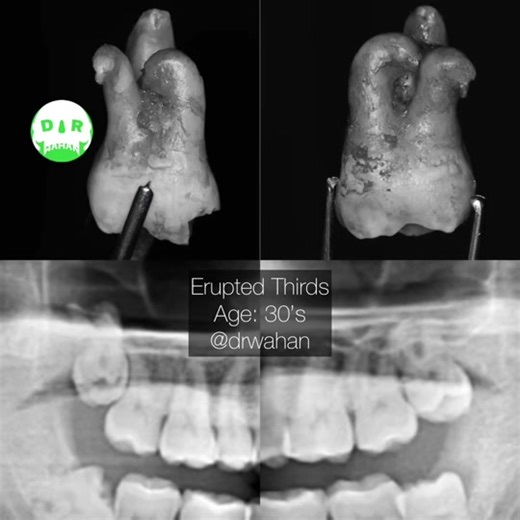

- Upper Wisdom Tooth

Extraction - Upper Wisdom Tooth

Upper Wisdom Tooth - Wisdom Tooth